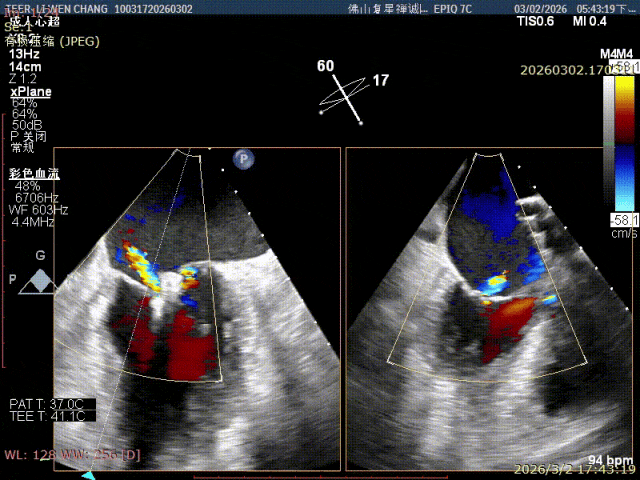

术前影像

X-plane 1区 后叶脱垂

X-plane1区 反流重度